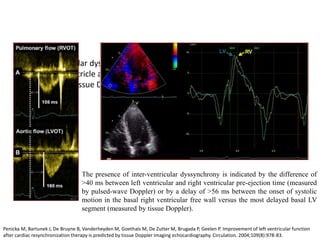

• Interventricular dyssynchrony refers to dyssynchrony between the left and

the right ventricle and can be measured using conventional pulsed-wave

Doppler or Tissue Doppler imaging

The presence of inter-ventricular dyssynchrony is indicated by the difference of

>40 ms between left ventricular and right ventricular pre-ejection time (measured

by pulsed-wave Doppler) or by a delay of >56 ms between the onset of systolic

motion in the basal right ventricular free wall versus the most delayed basal LV

segment (measured by tissue Doppler).

Penicka M, Bartunek J, De Bruyne B, Vanderheyden M, Goethals M, De Zutter M, Brugada P, Geelen P. Improvement of left ventricular function

after cardiac resynchronization therapy is predicted by tissue Doppler imaging echocardiography. Circulation. 2004;109(8):978-83.